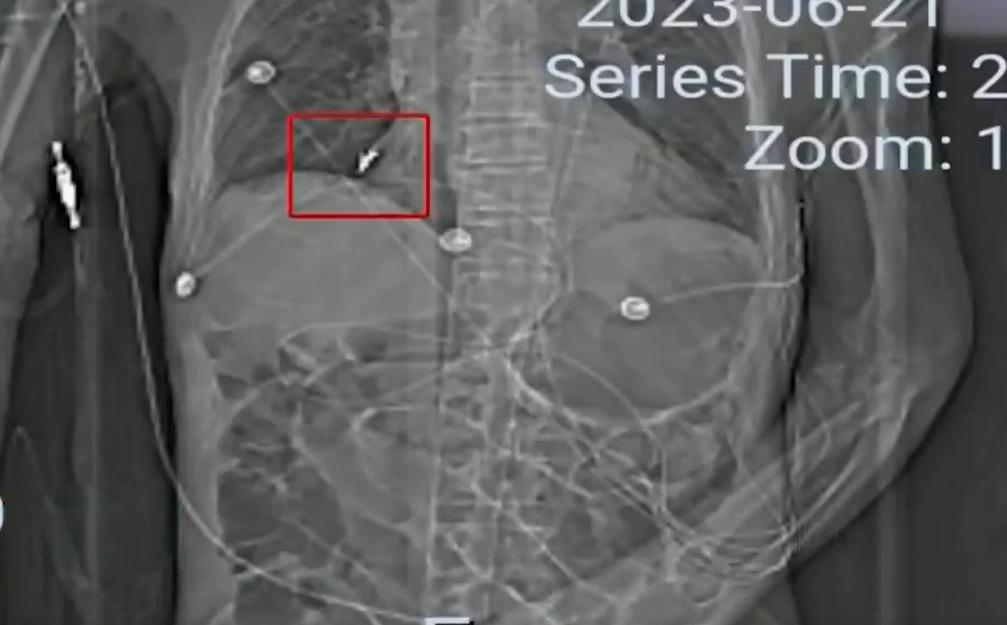

綜合報道,85歲姓孫的老翁,今年3月因胃口不好送院檢查,發現他消化道穿孔、重度貧血等疾病,第二日,院方為老翁進行手術,事後狀態亦好轉,不過,324老翁突然出現了呼吸困難的狀況,院方為他做插喉,當天下午,老翁家屬到醫院ICU探病時,醫生將一隻牙齒交給他們,指是為老翁做氣管插管時發現。家屬認為肺裡的牙很可能會給老翁帶來致命性傷害,但牙齒為何會進入胸腹腔內。網上影片可見醫院表示,老人在住院期間確實做了多次氣管插管,在插管前,醫務人員已對老人的牙齒做過相關檢查。詎料20日後,醫院又在父親的胸腹腔內發現了6隻牙齒和一個牙套。家屬表示,直到414日做支氣管鏡時,發現肺裡有一隻牙,再調查後在食道下端,快進入胃的地方又發現了5隻牙和一個牙套。

醫院提50萬不做醫療鑒定補償 家屬拒絕

醫生表示,老翁肺部的假牙形狀特殊,有鈎子,院方做了各種嘗試,最終都未能取出,另外,經過醫院治療,老翁胃部的狀況明顯得到了好轉,隨後就轉入了普通病房。不過沒多久,老翁出現了胃出血的情況,同時高燒不斷,肺部反復出現感染,直到老翁臨終,肺裡的牙都未取出。家屬指,自從牙齒進入肺部以後,老翁的肺部就一直有炎症,高燒不斷,院方也一直在想辦法把牙齒取出,過程中不僅加重家屬的經濟負擔,還讓老人家受罪。院方提出給予50萬元人民幣作不做醫療鑒定的補償,家屬則指,老翁住院期間不算醫保,自費已花掉逾30萬元,其中部分費用用於取牙齒及治療肺部怠染,認為補償金額無法接受。目前,雙方仍就補償金額協商。